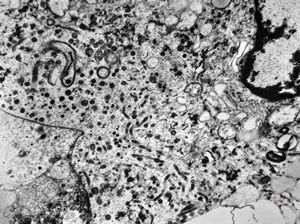

M,3y. | globoid leukodystrophy of Krabbe - n.suralis